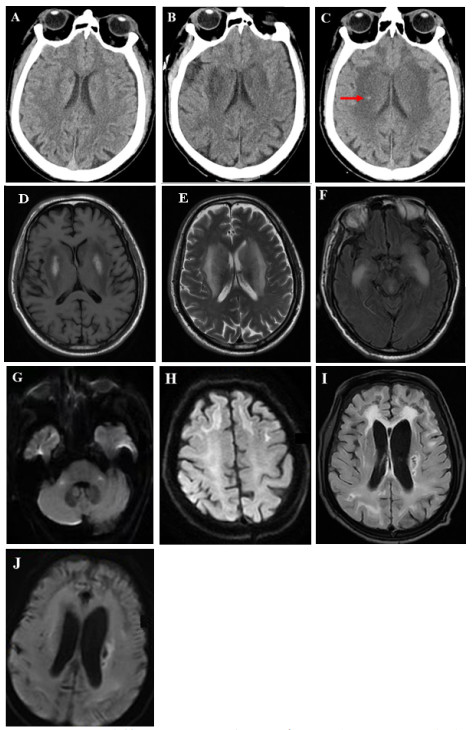

| 注:(A)入院第1天CT示双侧脑室旁见对称性月晕状稍低密度影;(B)入院第5天CT示双侧基底节区对称性低密度灶,较前显著;(C)入院第15天CT示双侧基底节区病灶较前密度减低,新增小片状高密底影,提示小出血灶(箭头所示);(D-H)入院第9天MRI示双侧基底节区呈对称性长T1长T2信号,伴有脑肿胀;FLAIR序列双侧颞叶深部对称性高信号影;DWI序列双侧桥臂、额叶皮层下白质多发斑点片状及条片状高信号影;(I-J)出院第6个月MRI示FLAIR和DWI序列双侧基底节区仍见多发斑点状及条片状异常信号影,较前高信号减低,范围缩小,脑室系统明显扩大,皮层萎缩 图 1 本例患者头颅影像学动态演变 |

患者入院后即行血液灌流(3次/d,共2 d)清除毒物、连续性肾脏替代治疗纠正内环境紊乱、血管活性药物维持血压、补液促进毒物排泄及对症支持等治疗。中毒后第5天,患者仍深昏迷,GCS评分2T(E1VTM1)。复查头颅CT:双侧基底节区对称性低密度灶,较前片明显,见图 1B。中毒后第9天,意识状况仍无改善,检查头颅MRI:双侧额顶颞枕叶皮层下、基底节区、桥臂多发异常信号,伴脑肿胀,考虑中毒性脑病,见图 1D~图 1H;磁共振动脉自旋标记(arterial spin labeling, ASL):两侧额颞叶皮层下白质区对称性灌注增高,两侧基底节、小脑、枕顶叶对称性灌注减低,符合中毒性脑病改变,见图 2A~图 2C。针对意识障碍治疗予纳洛酮静脉滴注;针对脑水肿予20%甘露醇静脉滴注(每次150ml,第1周每8小时1次,第2周每12小时1次),甲泼尼龙静脉注射(每次40mg,第1周每日2次,第2周每日1次)。中毒后第7天行床旁气管切开,中毒后第15天呼吸循环稳定,停用呼吸机,但仍处于昏迷状态,无气道自洁能力,GCS评分5分(E2V1M2)。中毒后第15天复查头颅CT:双侧基底节区病灶较前密度减低,新增小片状高密度影,提示小出血灶,见图 1C。

患者中毒后第20天出院,并转至本地康复医院继续治疗,方案包括高压氧促进脑功能恢复、药物预防癫痫发作,辅以低频电刺激、电动起立床训练、针灸等康复治疗。康复过程中患者持续经鼻饲进食,大小便无法自控,中毒后第3个月GCS评分7分(E2V2M3)。坚持以上康复方案,中毒后第6个月,GCS评分10分(E3V3M4)。复查头颅MRI:双侧额顶枕叶皮层下可见少许斑点片状及条片状DWI稍高信号影,较前高信号减低,范围缩小,脑室系统明显扩大,皮层萎缩,见图 1I ~图 1J。磁共振ASL:双侧额顶枕叶、小脑半球灌注弥漫性减低,损害范围较前扩大,见图 2D~图 2F。动态随访,中毒后第10个月,患者意识状况稍改善,能自主睁眼,简单应答,对刺痛能明确定位,能经口进食,GCS评分12分(E4V3M5)。随访至中毒后第15个月,患者神经功能较前不再有显著变化。

中毒性脑病是由药物或毒物引起的中枢神经系统器质性病变,主要累及脑白质,同时也可侵犯灰质结构及部分神经核团,临床表现多样[6]。影像学检查对于中毒性脑病具有重要价值,能够明确病变范围及脑实质受累程度,并为临床诊疗方案提供关键依据。急性期的脑CT扫描常表现为皮层下白质弥漫性对称性低密度信号,脑组织肿胀[7];MRI在评估中毒性脑病方面比CT更为敏感,常表现为T2WI、FLAIR和扩散加权像(DWI)上皮层下白质对称性高信号病变,此外,某些毒物还会引起双侧小脑齿状核、苍白球、内外囊、丘脑出现异常信号强度[7-10]。本例哒螨灵中毒患者急性期主要表现为意识障碍,影像学提示双侧额顶颞枕叶皮层下、基底节区、桥臂多发病变,表明严重哒螨灵中毒所致神经系统损害累及范围较广。随访至半年后,上述神经系统损害在MRI上仍然存在,且伴随严重的皮层萎缩,脑室扩大,提示患者神经影像发生持续性不可逆性的损害。但患者经治疗后意识状况有一定程度好转,其GCS评分在出院后的康复过程中存在缓慢改善的趋势。已有报道在一氧化碳中毒性脑病的患者中,CT或MRI检查结果并不能准确反应病情的轻重和转归[11],这一结论与本案例相似。